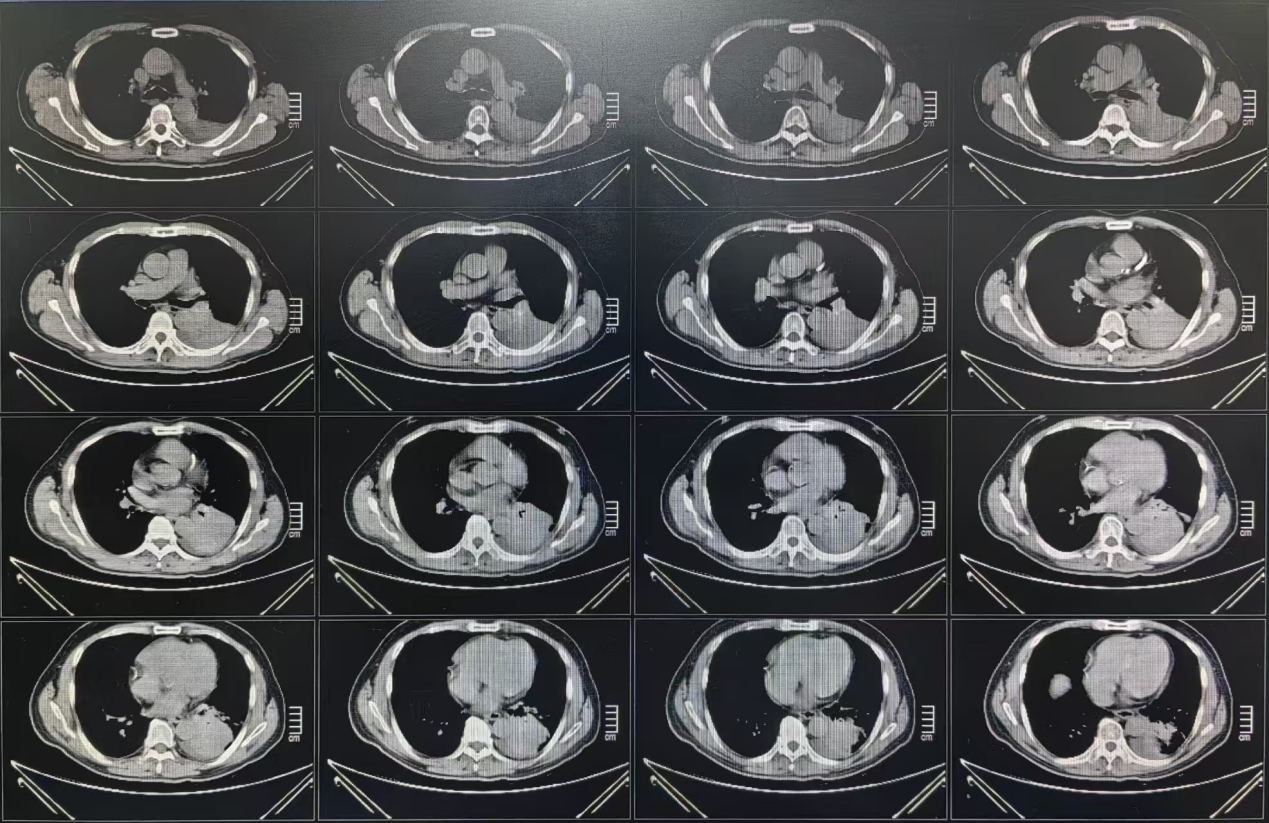

胸部CT结果

3. 2023年8月2日胸部CT示:左肺团块状高密度影(3.7*3.2cm),左肺癌性淋巴管炎可能。

1. 2023年5月19日胸部CT示:左肺团块状高密度影(4.2*2.9cm),可见毛刺及胸膜牵拉,周围肺野内可见絮片状高密度影。较2023年3月25日CT相比左肺下叶病灶略缩小。

1. 2023年10月17日胸部CT示:左侧胸膜稍增厚,左侧胸腔积液。

3. 2024年12月26日复查胸部CT示:(1)左肺下叶切除术后:吻合口旁软组织影,较大截面约3.4*2.5cm,较2024年8月16日新发,考虑复发可能,伴纵隔淋巴结增大;(2)左侧胸腔积液伴左肺膨胀不全;(3)左肺动脉肝低密度充盈缺损影,考虑肺栓塞。